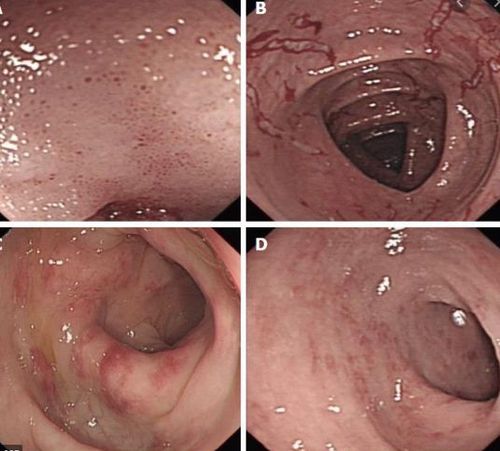

Đặc điểm lâm sàng của viêm dạ dày do bạch cầu ái toan bao gồm đau thượng vị, ngoại vi tăng bạch cầu ái toan trong máu, thiếu máu và giảm albumin máu. Nội soi bất thường bao gồm niêm mạc nốt, sung huyết, và loét / ăn mòn, nhưng niêm mạc có thể bình thường.

Tuy nhiên, một cách tiếp cận hợp lý là viêm đại tràng do bạch cầu ái toan phải là một chẩn đoán bệnh học lâm sàng, tương tự như viêm thực quản do bạch cầu ái toan, đòi hỏi cả hai triệu chứng có thể đề cập đến rối loạn chức năng đại tràng và sinh thiết ruột kết cho thấy thừa bạch cầu ái toan. Sinh thiết ruột kết cho thấy bạch cầu ái toan mật độ lớn hơn bình thường. Hầu hết những bệnh nhân đó đều có các triệu chứng, chủ yếu là tiêu chảy và đau bụng, nhưng khoảng một phần ba không có triệu chứng. Đã báo cáo bất thường nội soi bao gồm xuất huyết, mất niêm mạc, tổn thương màu trắng, niêm mạc hạt nhợt nhạt và loét áp-tơ. Một số nghiên cứu đã ghi nhận rằng lượng bạch cầu ái toan dư thừa có thể được tìm thấy trong sinh thiết niêm mạc từ những bệnh nhân bị bệnh viêm ruột IBD.